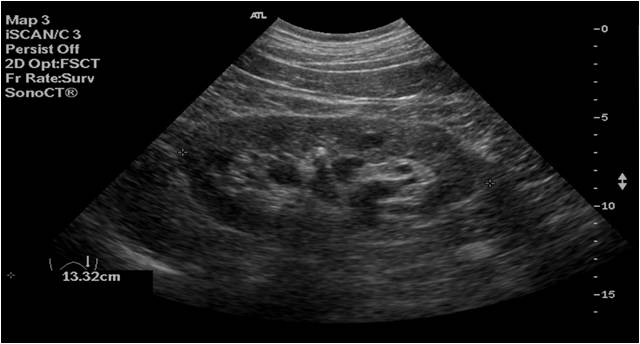

4

En esta imagen puedes ver una imagen hiperecogénica muy densa que parece una litiasis, pero llamativamente no deja sombra acústica posterior. Tiene una explicación, en la pirámides renales (flechas rojas) se puede acumular calcio en forma de «leche cálcica» que no tiene la densidad apropiada para dejar la sombra acústica, es decir, en vez de ser piedra es un tipo de líquido denso con mucha cantidad de calcio en su composición, por eso tiene una línea de nivel hidro-hidro.